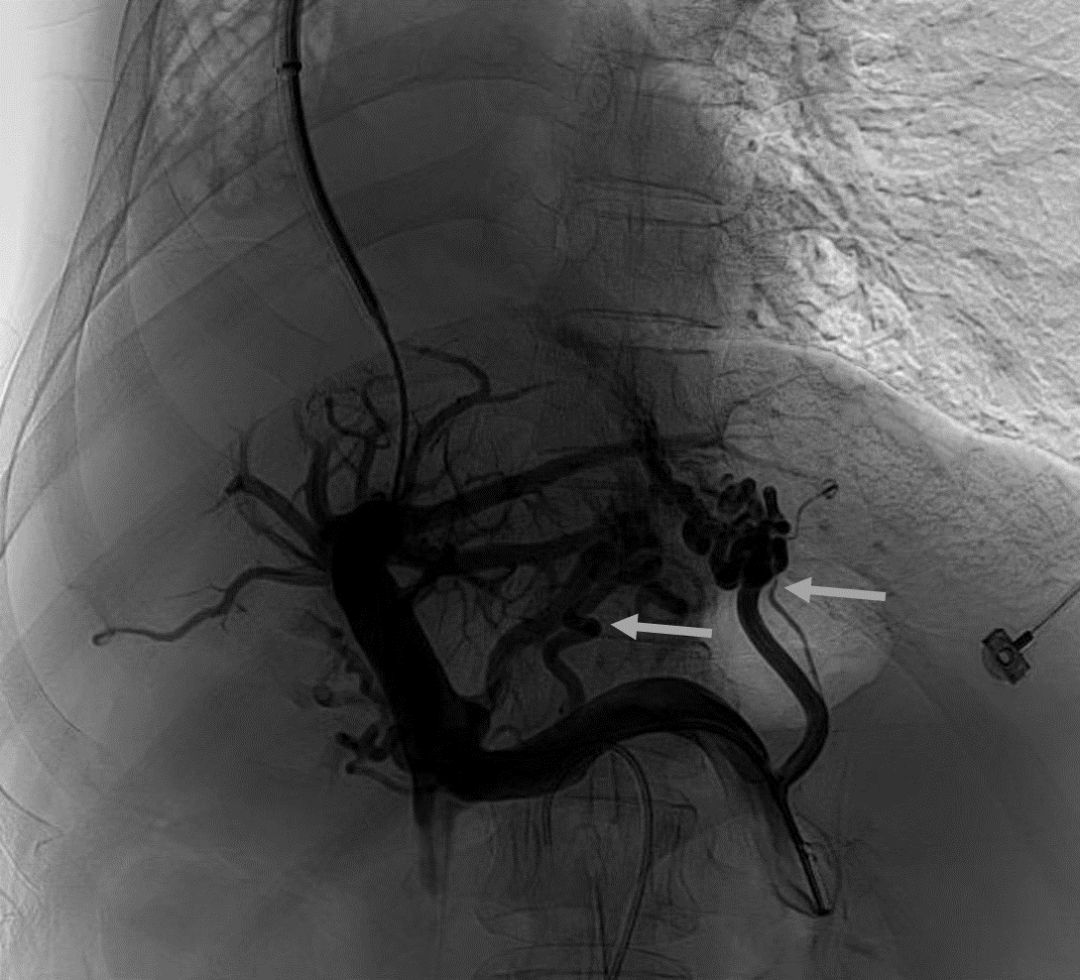

韓國宏教授介紹,TIPS手術(shù)是通過在肝靜脈與門靜脈之間的肝實(shí)質(zhì)內(nèi)建立分流通道,通過降低門靜脈壓力來預(yù)防和治療因門靜脈高壓引起的食管胃底曲張靜脈破裂出血或頑固性腹水。該手術(shù)不用開刀、創(chuàng)傷小、操作過程復(fù)雜、技術(shù)難度大、安全風(fēng)險(xiǎn)高,是目前外周血管介入中難度最大的手術(shù)之一。再加上人群中右位心發(fā)病率極低(約萬分之一),經(jīng)查閱文獻(xiàn),在國內(nèi)外尚未有類似病例報(bào)道,無經(jīng)驗(yàn)參考。在右位心基礎(chǔ)上行TIPS術(shù),無疑是難上加難。我們反復(fù)研究患者肝臟及心血管的特殊情況,詳細(xì)討論了手術(shù)方案,決定放棄常規(guī)的肝靜脈穿刺,另辟蹊徑,選擇高難度高風(fēng)險(xiǎn)的肝后段下腔靜脈穿刺門靜脈左支,憑借多年的經(jīng)驗(yàn)和嫻熟的技術(shù)最終成功的在下腔靜脈與門靜脈之間放置了TIPS專用支架,術(shù)后門靜脈壓力梯度從術(shù)前的19mmHg降至3mmHg,曲張靜脈消失,解決了困擾曹女士多年上消化道出血的困擾?;颊咝g(shù)后第二天即可正常下床活動。